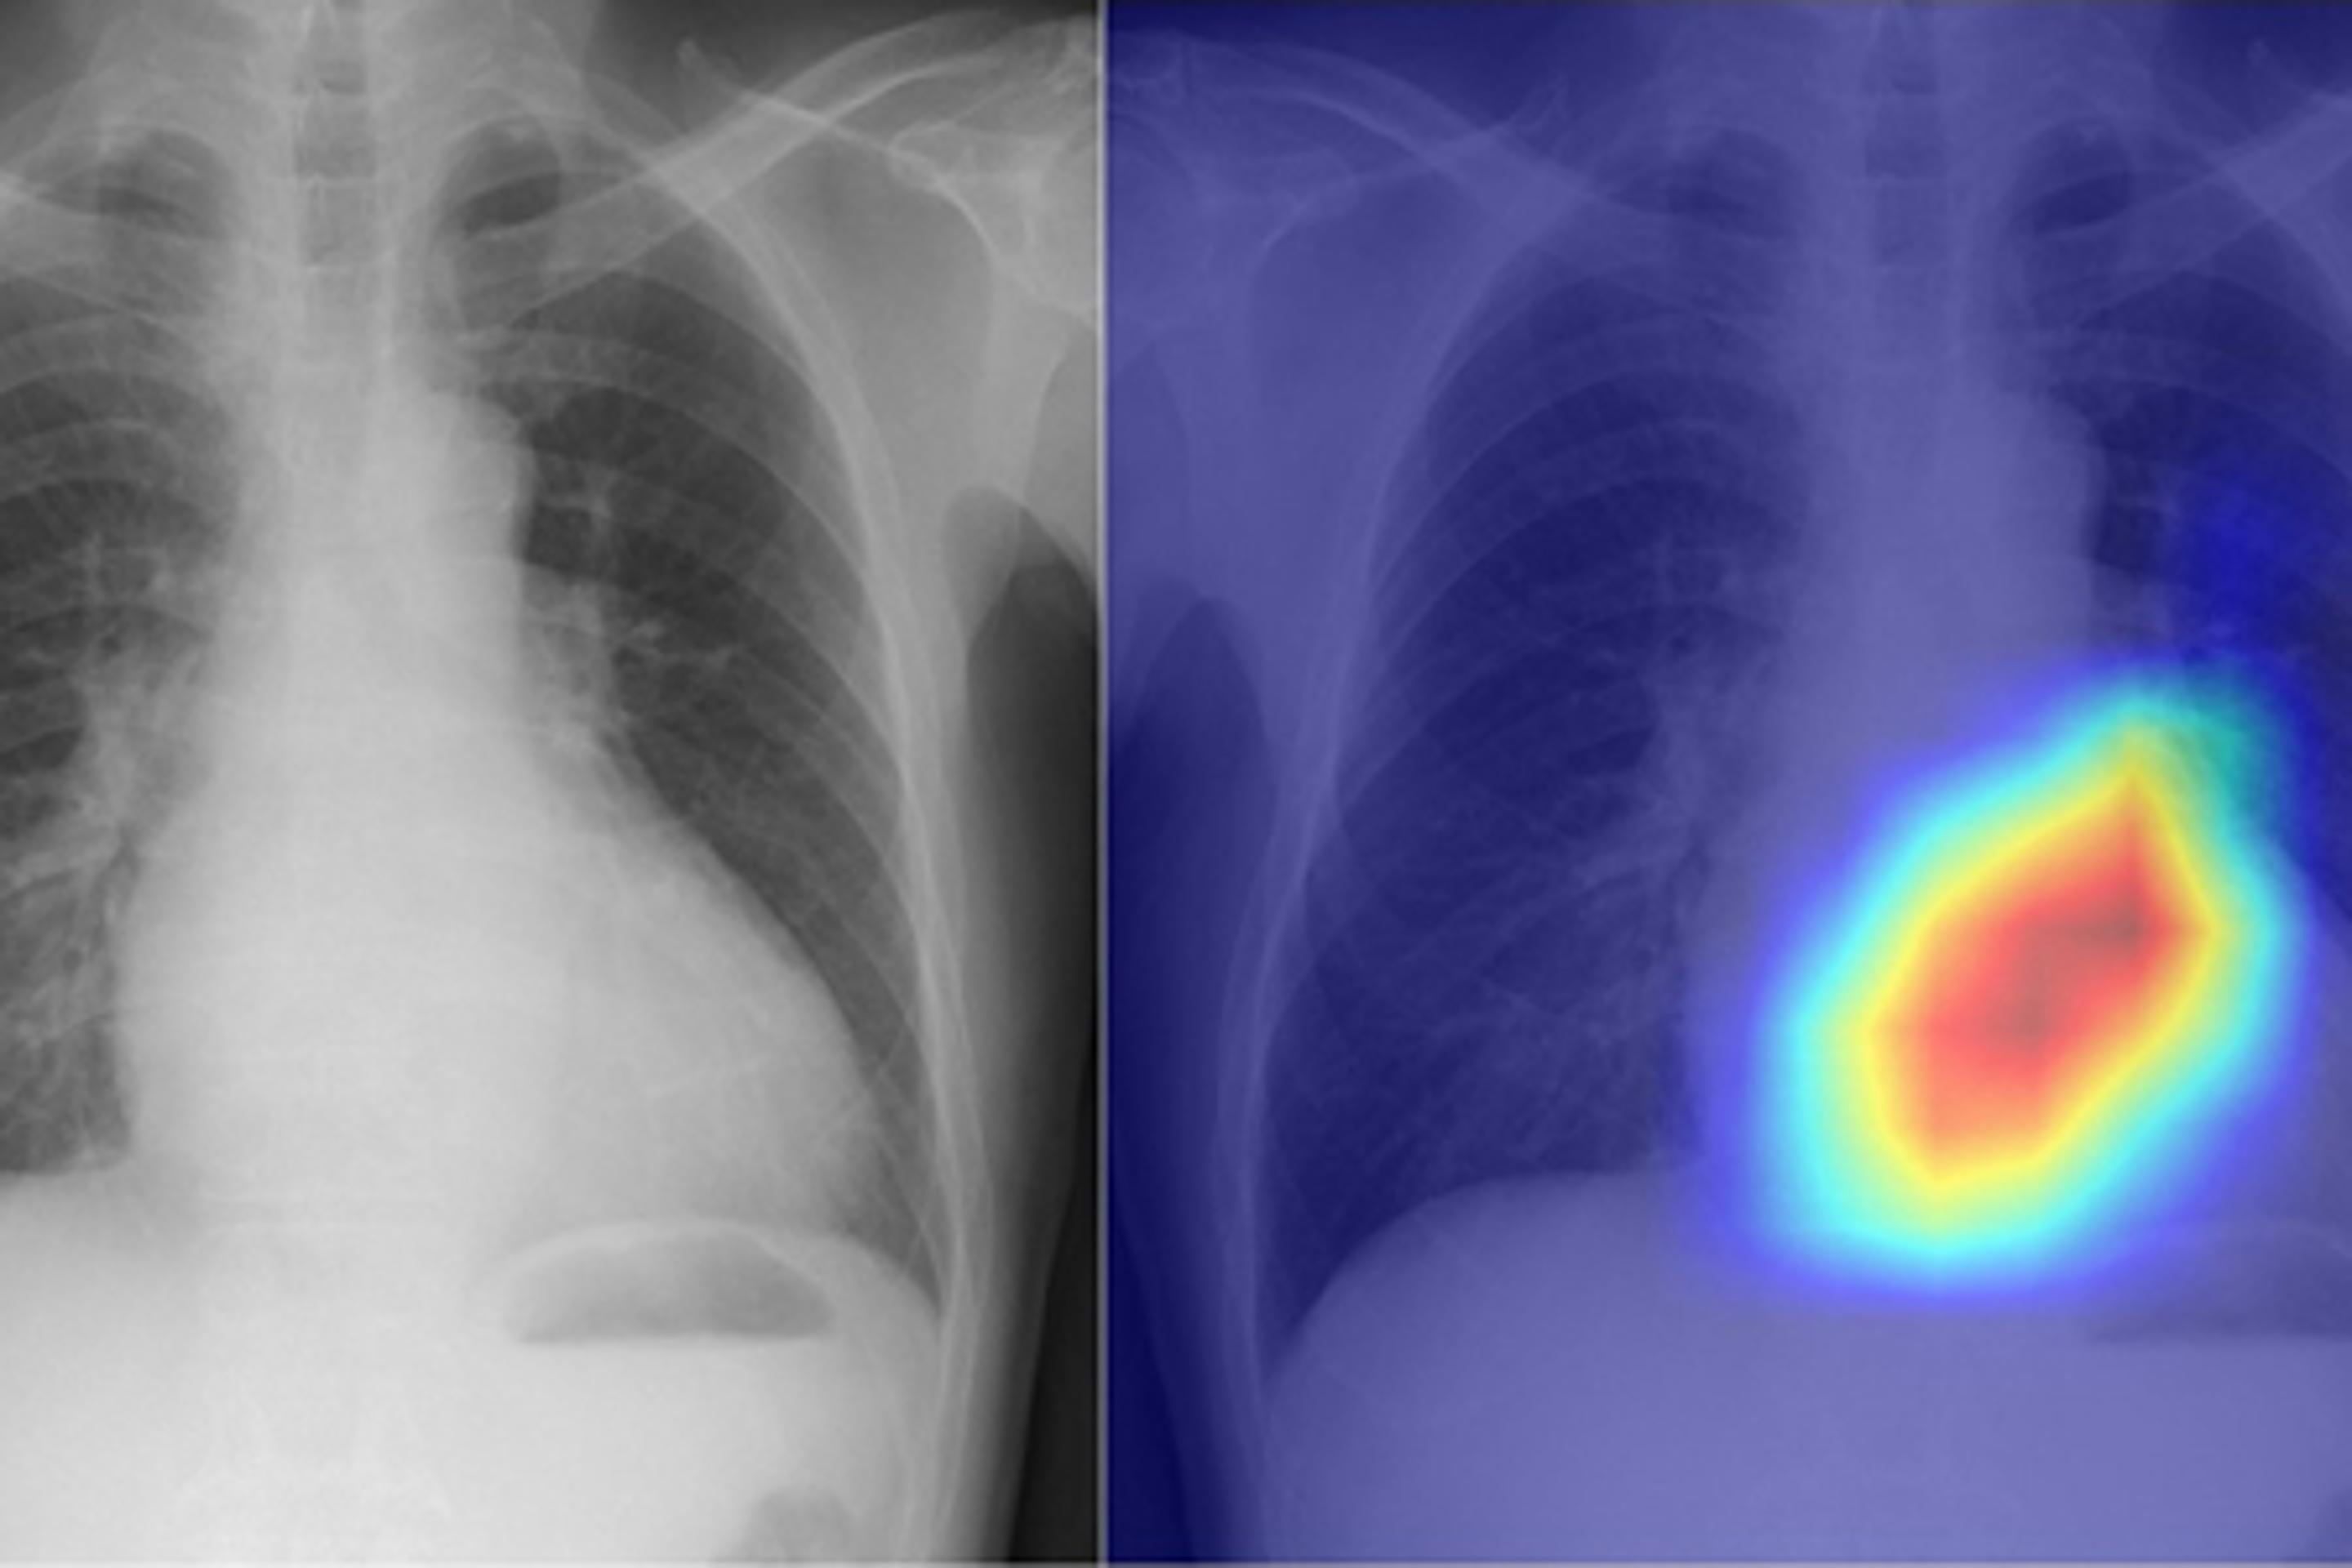

现在,来自大阪市立大学的研究人员招募了一个深度学习的人工智能模型,将简陋的胸部X光检查转变为一个更详细的诊断工具。

研究人员用2013年至2021年期间从四个机构的16946名患者那里获得的与22551张超声心动图相关的胸部X光片来训练深度学习模型。他们使用了来自多个机构的数据,以减少人工智能产生偏颇结果的风险。

X光片被设定为输入数据,超声心动图被设定为输出数据,模型被训练为学习连接两个数据集的特征。在测试他们的深度学习模型时,研究人员发现,它可以精确地将六种类型的瓣膜性心脏病分类。曲线下面积(AUC)--表示人工智能模型区分类别的能力的评分指数--在0.83至0.92之间。AUC的数值范围从0到1;越接近1越好。